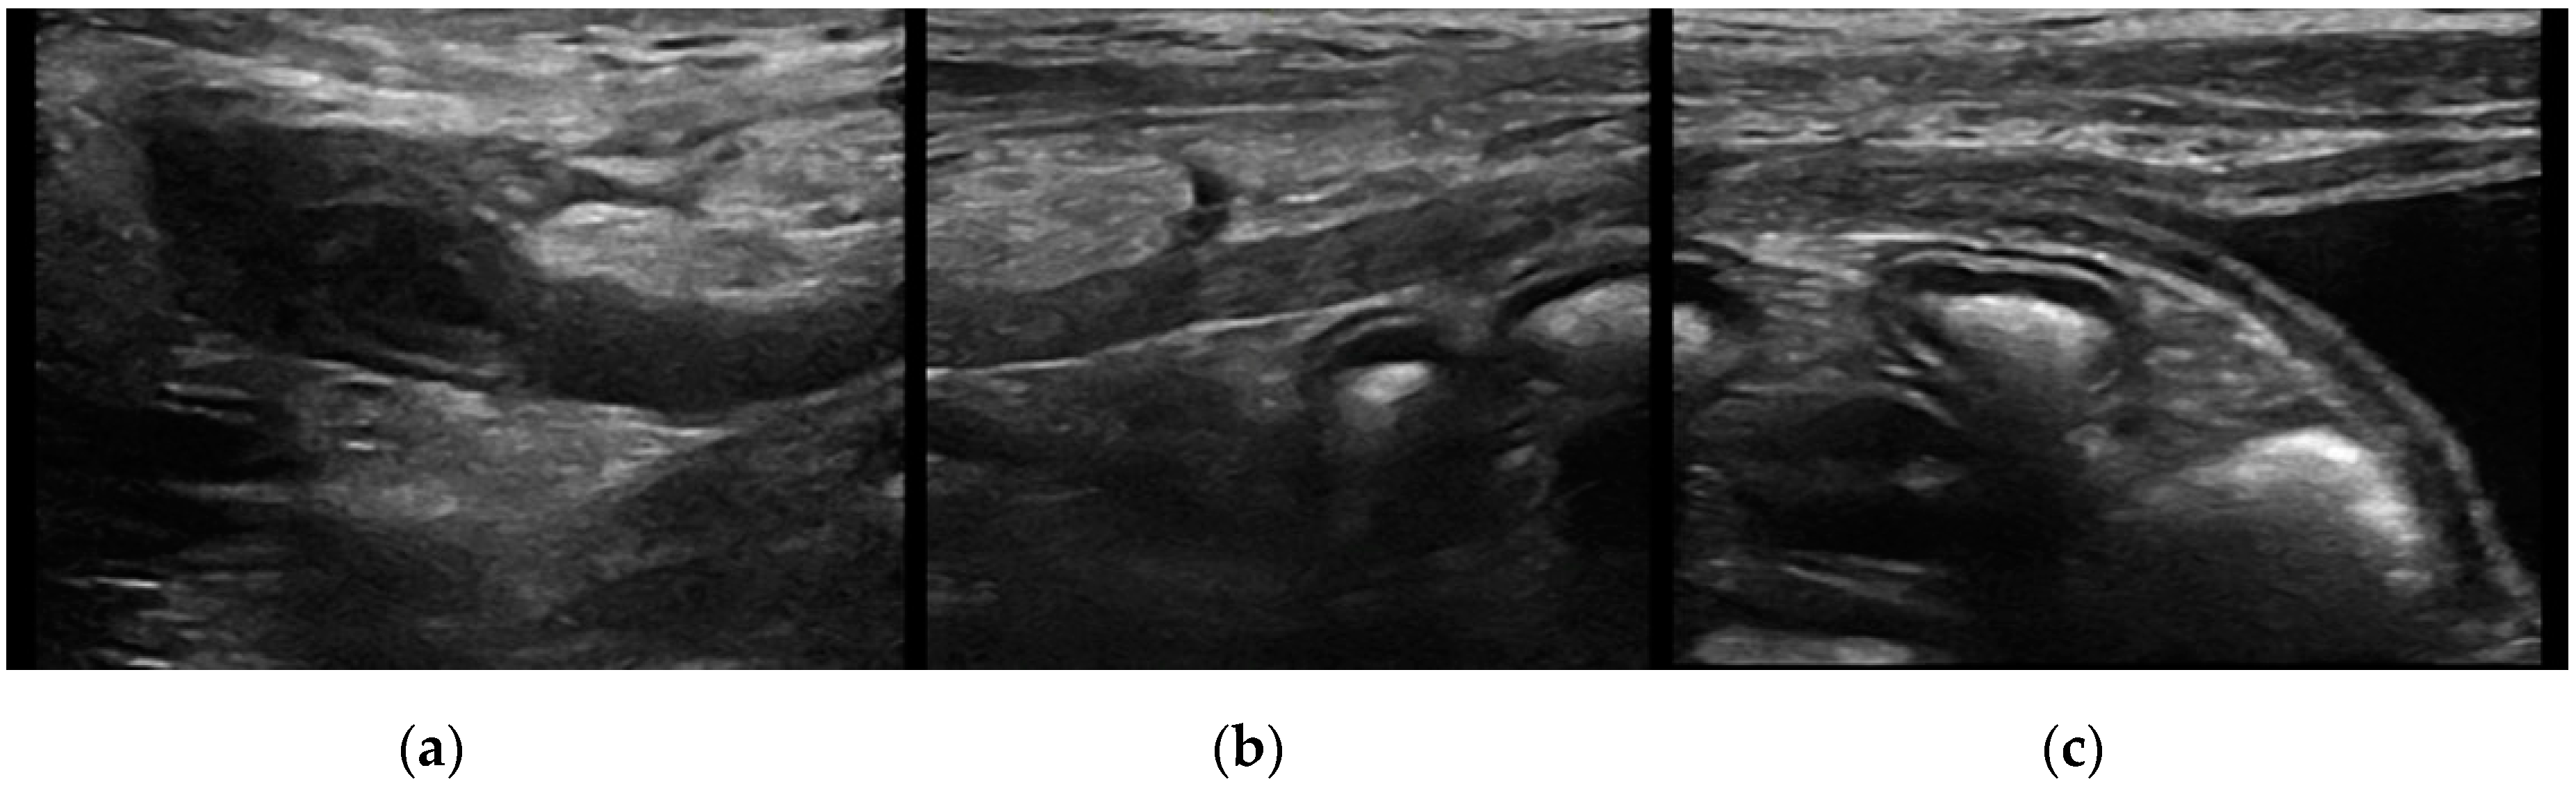

Extramural vesicourachal diverticulum was diagnosed in 20.0% of cats and 18.4% of dogs. Four out of 19 were of large dimensions and extended 1 to 2 cm cranially to the serosa of the urinary bladder apex; 3/19 appeared 0.5–1 cm in diameter, while 12/19 were smaller than 0.5 cm. The wall appeared as a thin hyperechoic line and the content was similar to that of the bladder (Figure 3).

Figure 3. Longitudinal ultrasound image of the urinary bladder in a cat, showing the presence of a small (<1 cm diameter), well-defined, fluid-filled, anechoic structure, protruding beyond the serosal surface of the cranioventral bladder wall, consistent with extramural vesicourachal diverticulum. The bladder presents a moderate, diffuse, thickening of the wall, with an irregular mucosal surface. A moderate amount of echogenic sediment is present in the lumen. Shadowing hyperechoic material adhered to the ventral bladder wall mucosa is also observed, which may represent congealed mineralized sediment.